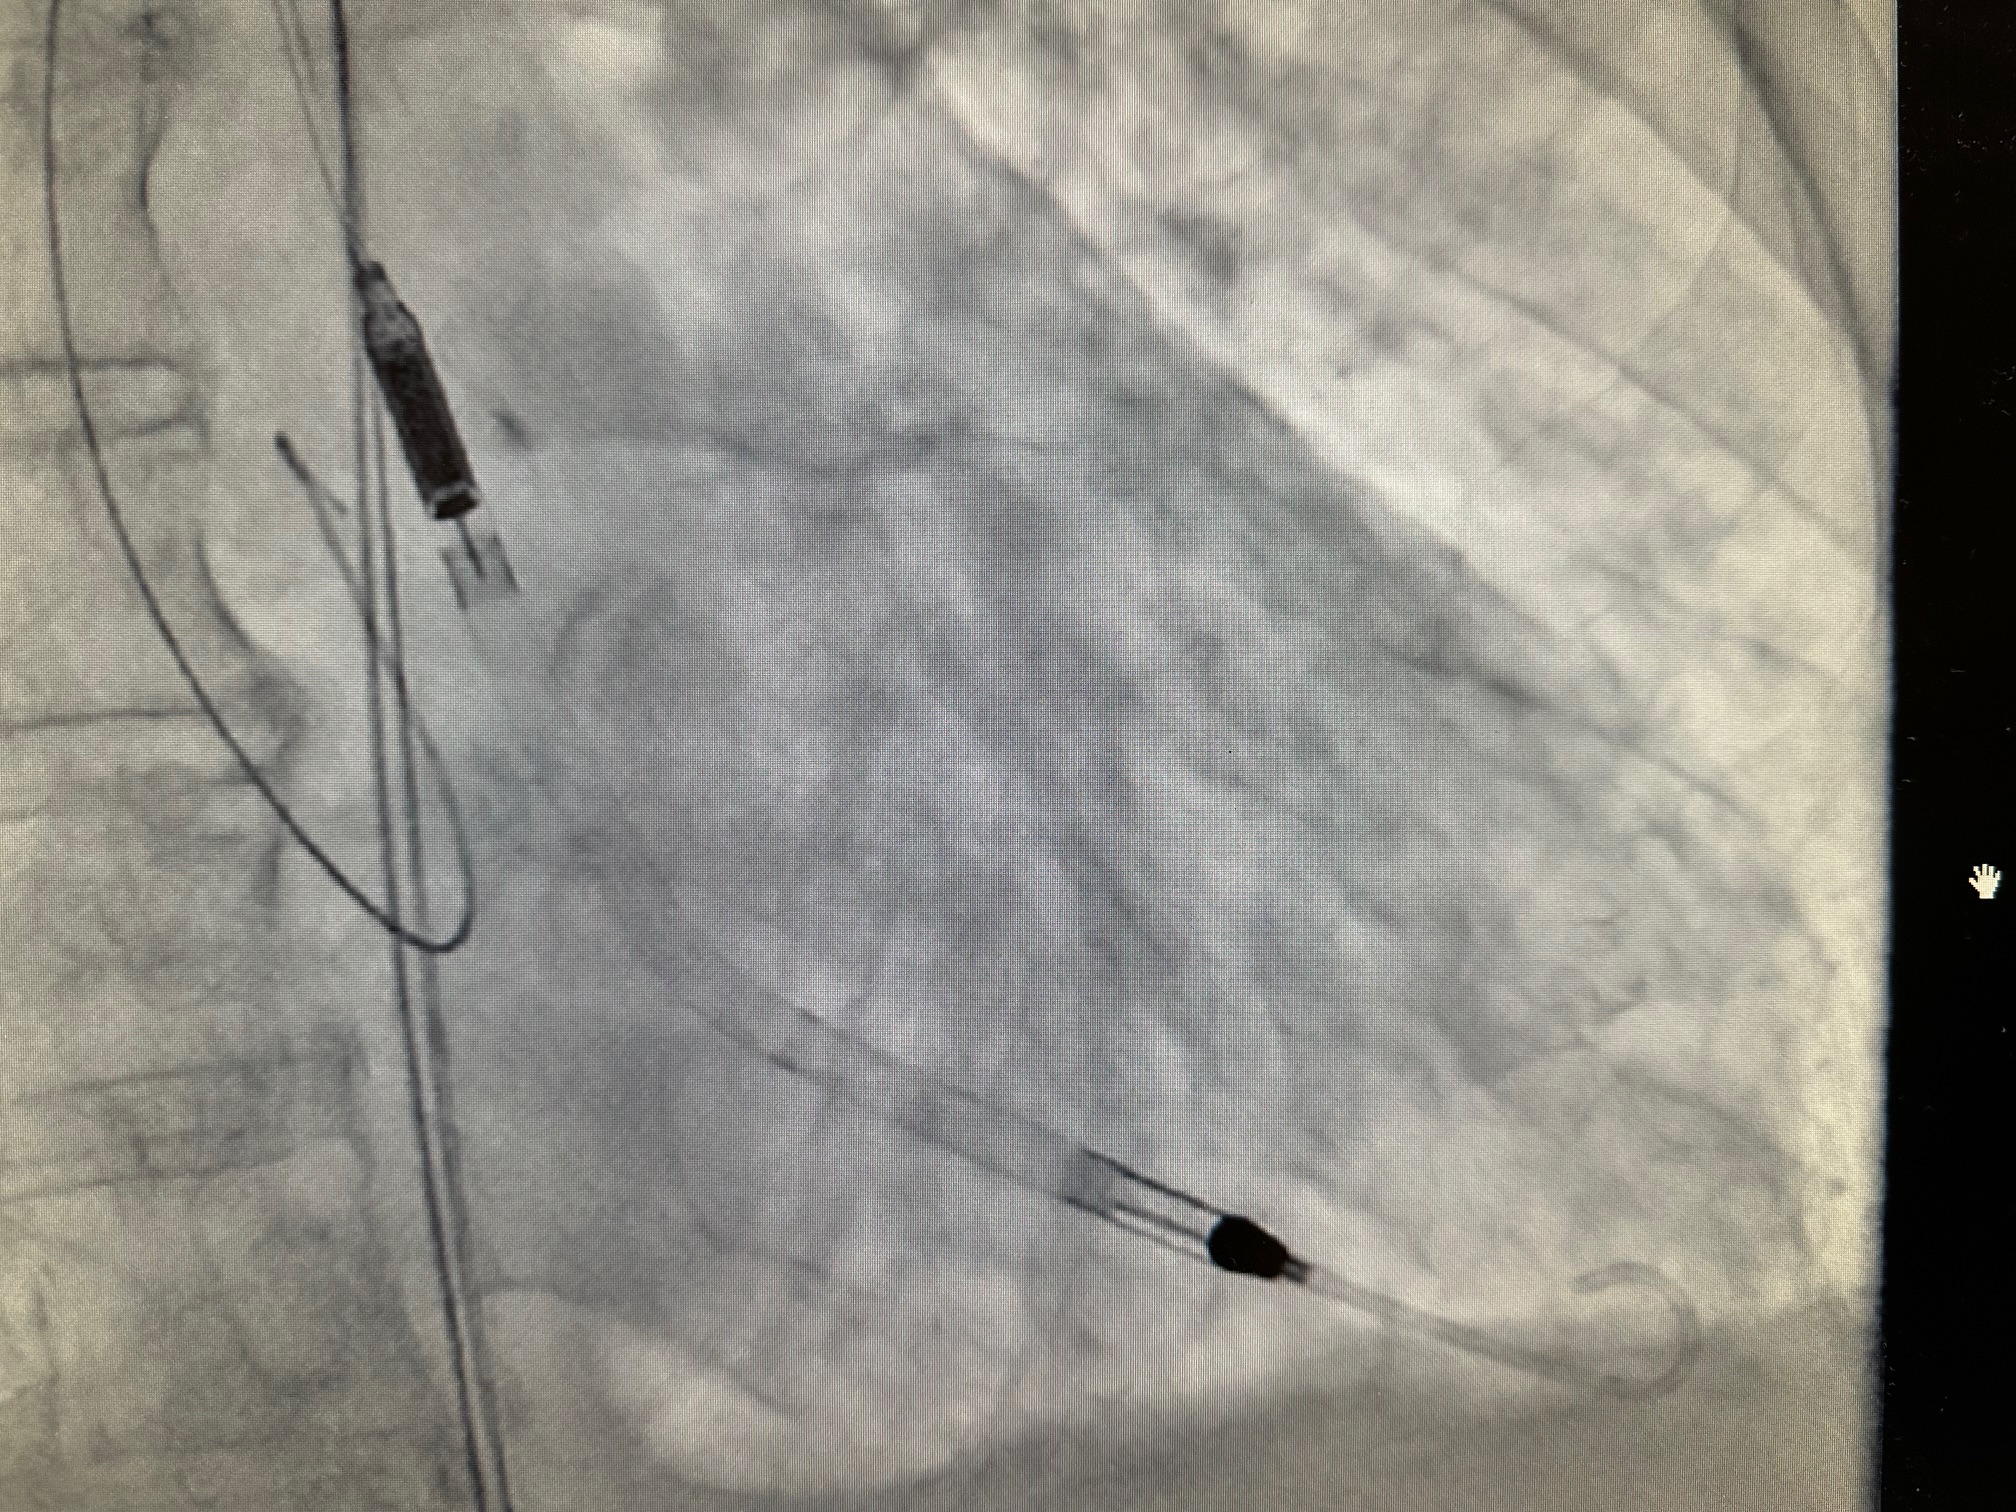

Na Odjelu intervencijske kardiologije, pod vodstvom dr. med. Mihajla Kovačića, specijalista interne medicine i subspecijalista kardiologije, izvedena je prva kompleksna intervencija uz pomoć novog uređaja za potporu srčane funkcije – Impella CP.

“Impella CP koristi tehnologiju perkutane srčane pumpe koja se kroz femoralnu arteriju uvodi u lijevu srčanu klijetku i pruža potporu radu srca kod visokorizičnih zahvata i srčanog zatajenja. Uređaj osigurava protok krvi do 4.3 litre u minuti, čime značajno smanjuje opterećenje srca i pomaže pri održavanju cirkulacije.

Ova tehnologija predstavlja vrhunac suvremene medicinske skrbi za pacijente u kardiogenom šoku ili pri izvođenju visokorizičnih PCI zahvata.